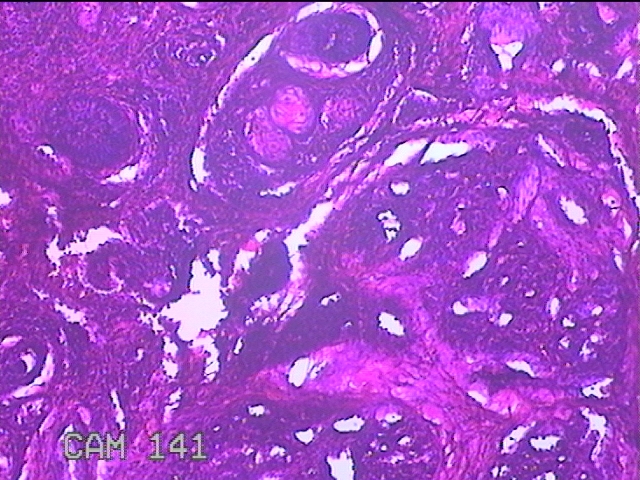

右侧耳后结节

灰白暗红色结节1.2x0.7x0.3cm一个,表面糜烂,切开结节呈实性,切面灰白暗红色,质软。